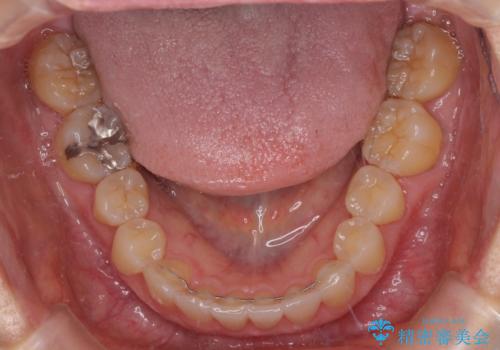

前歯のクロスバイト インビザライン矯正で改善

- むし歯治療を契機に、長年気にしていた前歯のクロスバイトの改善を希望された患者様です。

汚れが溜まりやすく、歯ぎしりがうまくできないため、インビザラインを用いて矯正治療を行うこととしました。

インビザラインによる前歯のクロスバイトの改善は、治療期間中に前歯でしか咬めない時期が続いたり、歯肉退縮や歯髄壊死のリスクが高まったりと、治療中にトラブルを抱えることがあります。

特に上顎側切歯(真ん中から2番目の歯)が舌側に引っ込んでいるケースは、インビザラインでは改善しきれないことがあると言われています。